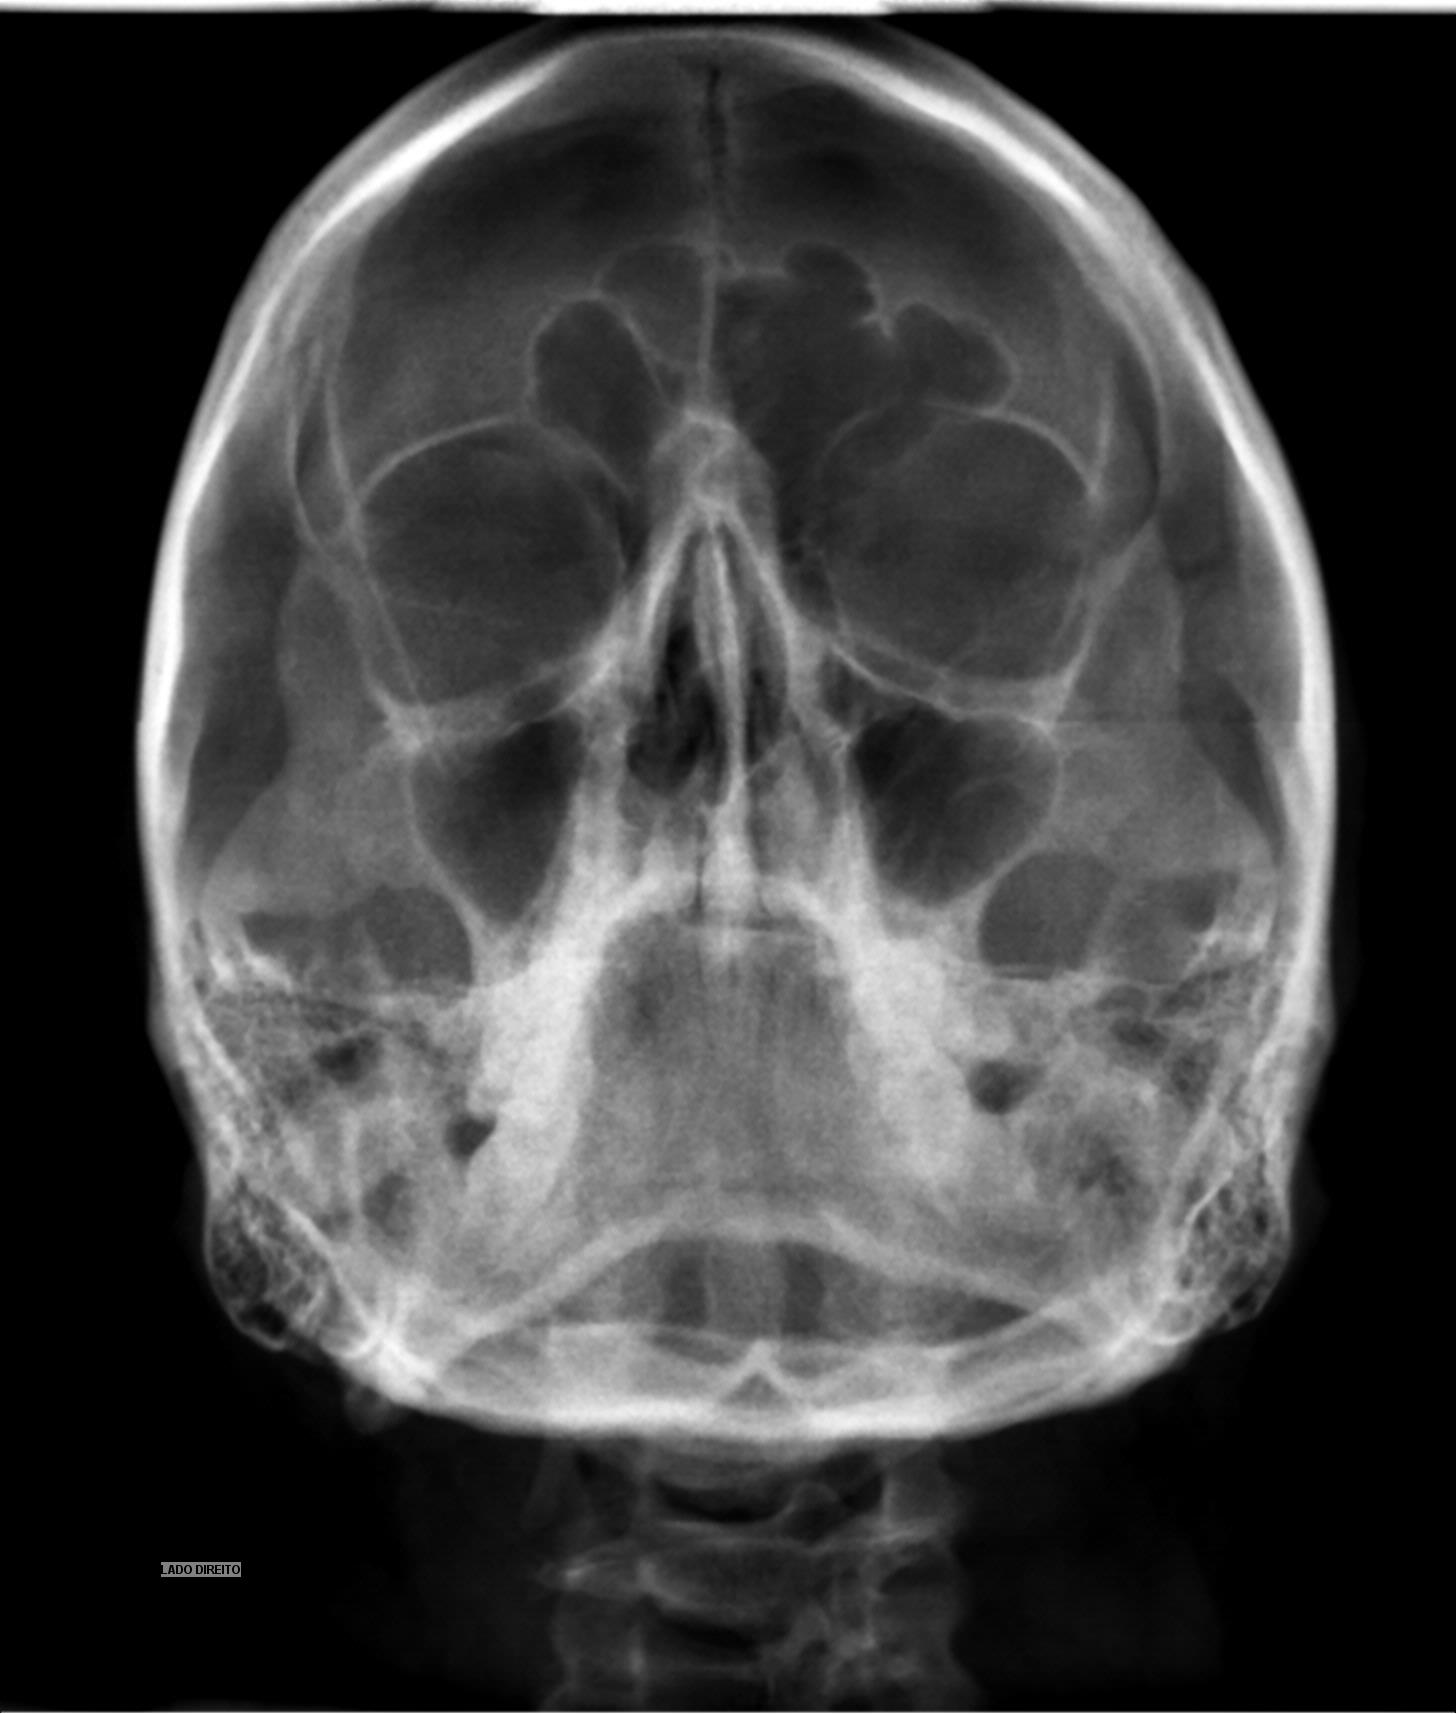

Raios X Seios Da Face – Método De Caldwell - Concursos Já Brasil

concursosjabrasil.com.br

concursosjabrasil.com.br